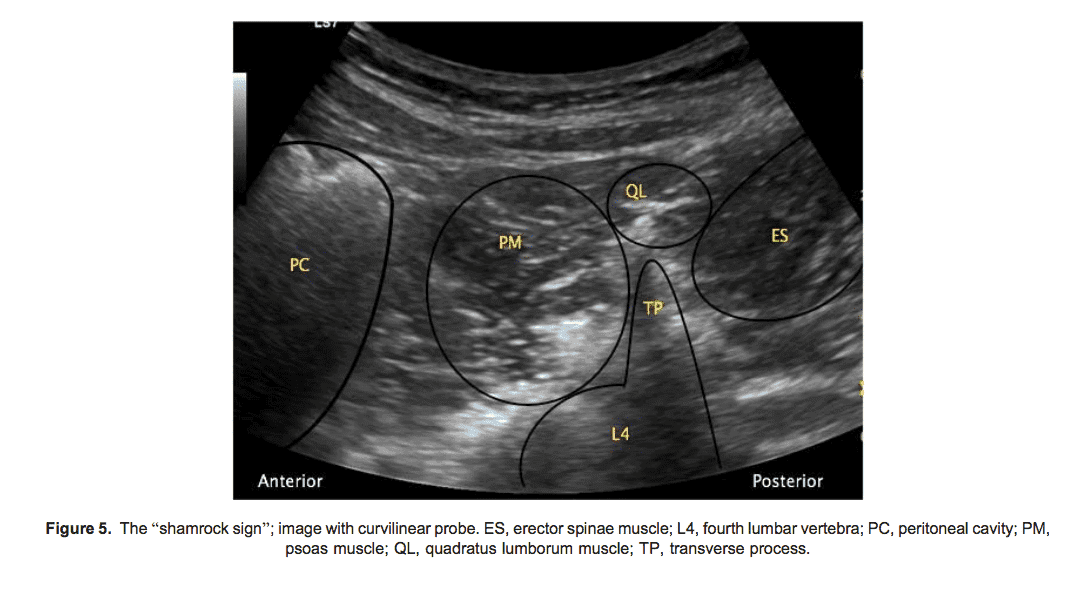

Для виконання трансм'язового QL-блоку квадратного поперекового м'яза використовують конвексний датчик, який розташовують у поперечній площині на фланку пацієнта, вище гребеня клубової кістки, та зміщують назад для ідентифікації m. quadratus lumborum.

У візуалізації може допомогти «знак трилисника»: стебло утворює поперечний відросток хребця L4, тоді як задній листок — м'яз випрямляч хребта (m. erector spinae), латеральний — квадратний м'яз попереку (m. quadratus lumborum), а передній — поперековий м’яз (m. psoas major).

Ціль для ін'єкції — фасціальний простір між m. quadratus lumborum і m. psoas major. Голку вводять за допомогою техніки in-plane від заднього або переднього краю датчика через m. quadratus lumborum. В ідеалі результатом є поширення розчину місцевого анестетика від місця введення (в межах фасціального простору між m. quadratus lumborum і m. psoas major) до паравертебрального простору.